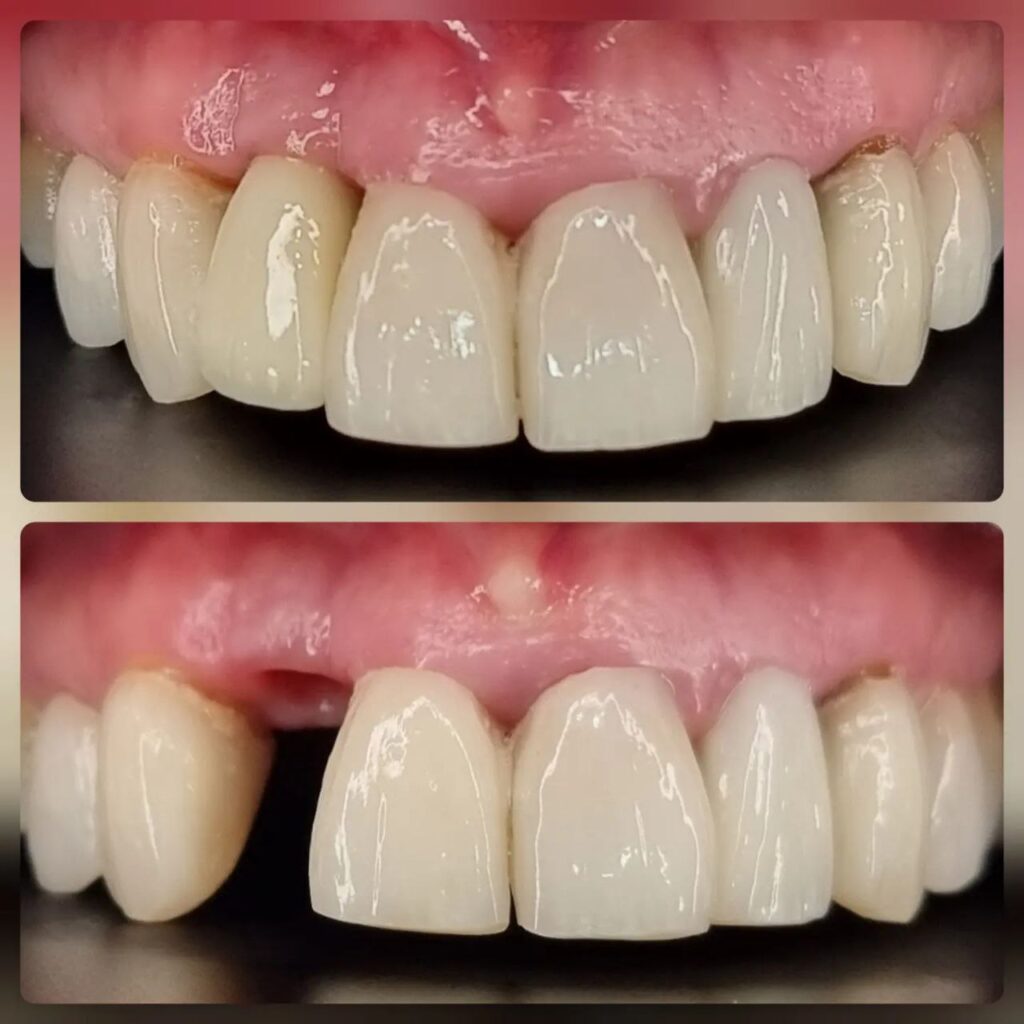

کاشت ایمپلنت دندان

اطمینان حاصل کردن از اینکه دندانهایتان به نحوی زیبا و طبیعی جایگزین شدهاند، از اهمیت بسیاری برخوردار است. ایمپلنت دندان به عنوان یک روش درمانی دائمی در دندانپزشکی شناخته میشود که حاصل آن، یک دندان زیبا و طبیعی در دهان شما خواهد بود.

هرچند که این روش درمانی هزینهی بیشتری نسبت به روشهای دیگر دارد، اما ارزش زیبایی که ایجاد میکند، قابل انکار نیست. ایمپلنتها به قدری شبیه به دندانهای طبیعی هستند که به سختی میتوان آنها را از دیگر دندانها تشخیص داد.